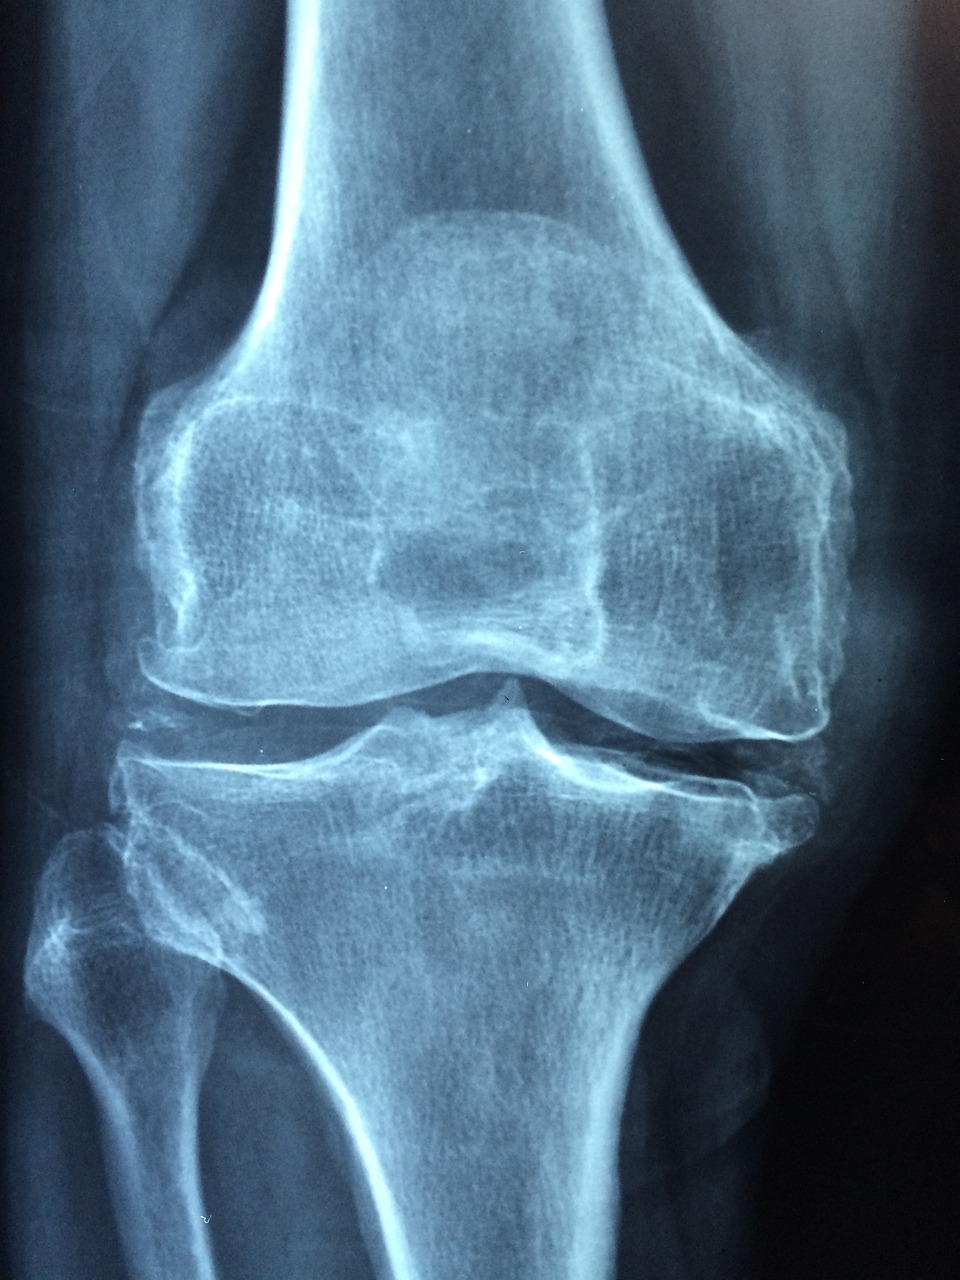

퇴행성 관절염은 65세 이상 노인의 약 70~80%가 겪는 흔한 질병입니다. 특히 무릎은 체중 부하가 심한 부위이기 때문에 관절이 닳고, 물렁뼈가 손상되면서 통증과 부종이 생깁니다. 이럴 때 근본적인 해결책은 바로 무릎 인공관절 수술입니다. 인공 관절을 삽입해 통증을 줄이고 기능을 되살리는 방식입니다.